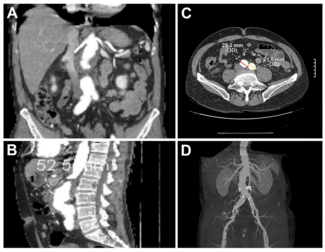

A 76-year-old man with hypothyroidism, chronic obstructive pulmonary disease, and coronary artery disease presented with dyspnoea facial puffiness, and bilateral pitting pedal oedema for the past 3 months. He had undergone percutaneous...